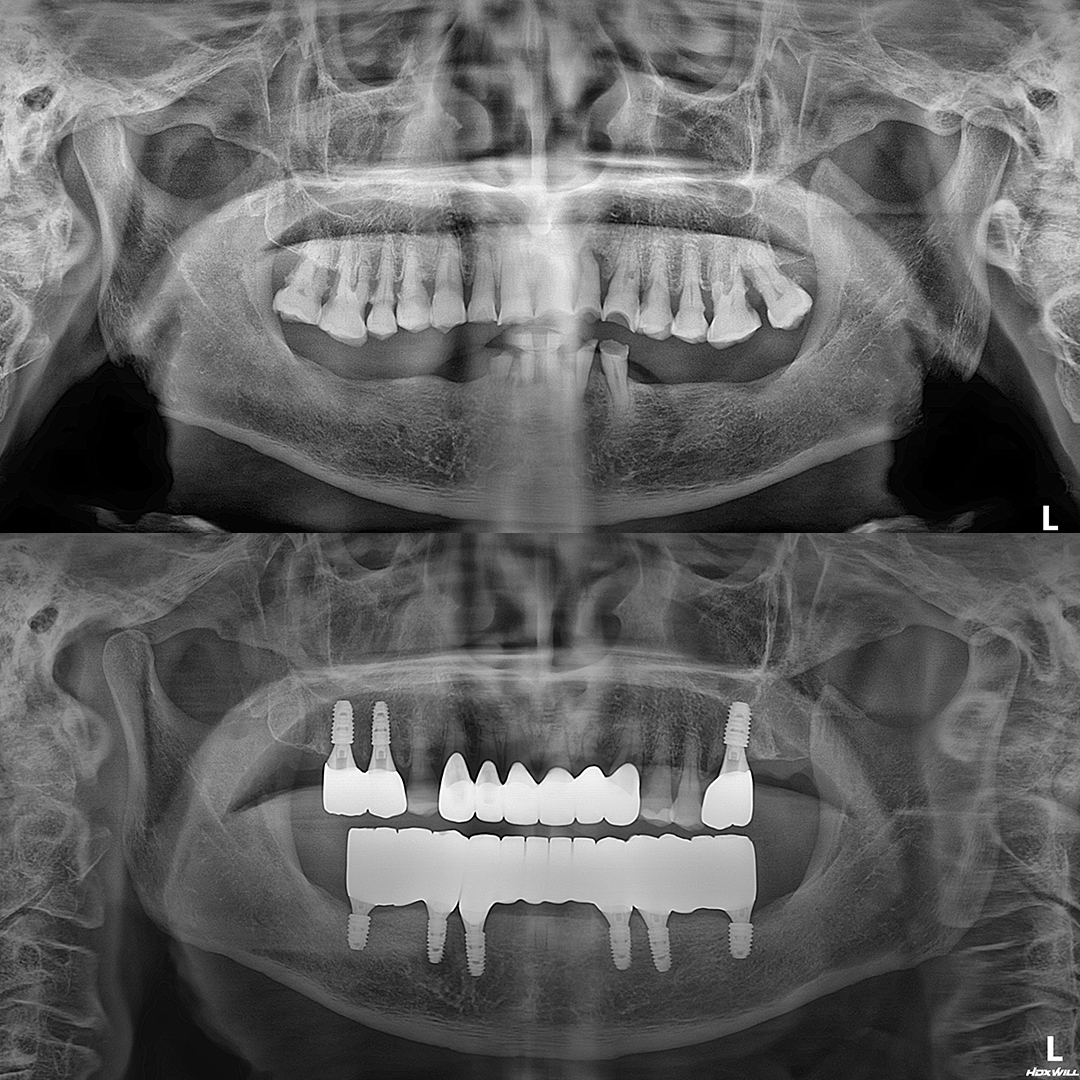

평균 악당 30분의 빠른 식립시간, 치료 케이스 다수 보유

전체 임플란트

상·하악 전체 치아를 대체하는 임플란트로 최소한의 식립을 통해

자연치아와 비슷한 기능을 수행할 수 있도록 합니다.